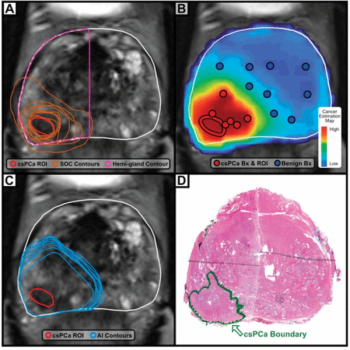

Artificial intelligence (AI) assisted contouring of prostate cancer demonstrated superior balanced accuracy than manual standard-of-care contouring and hemigland contouring with MRI, according to a new study.